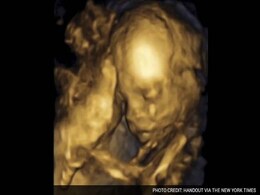

16 साल की उम्र में पता चला ‘कभी मां नहीं बनेगी’, बिना गर्भाशय के जन्मी महिला ने दिया ‘मिरेकल बेबी’ को जन्म

ब्रिटेन में मृत डोनर के गर्भाशय ट्रांसप्लांट के बाद बिना गर्भाशय के जन्मी महिला ने स्वस्थ बच्चे को जन्म दिया है. यह मेडिकल क्षेत्र की ऐतिहासिक और प्रेरणादायक सफलता मानी जा रही है.

यूके के केंट में रहने वाली ग्रेस बेल जन्म से ही बिना काम करने वाले गर्भ (non-viable womb) के पैदा हुई थीं. ग्रेस को एक मृत महिला डोनर से गर्भ ट्रांसप्लांट किया गया.

ब्रिटेन में हुआ चमत्कार, प्रत्यारोपित गर्भाशय से जन्मा पहला बच्चा, मेडिकल की दुनिया में कायम की नई मिसाल

ब्रिटेन में एक ऐसा चमत्कार हुआ है जिसने मेडिकल की दुनिया में एक नया इतिहास रच दिया है. ब्रिटेन की एक महिला ने ट्रांसप्लांट यूट्रस से एक हेल्दी बच्चे को जन्म दिया है.